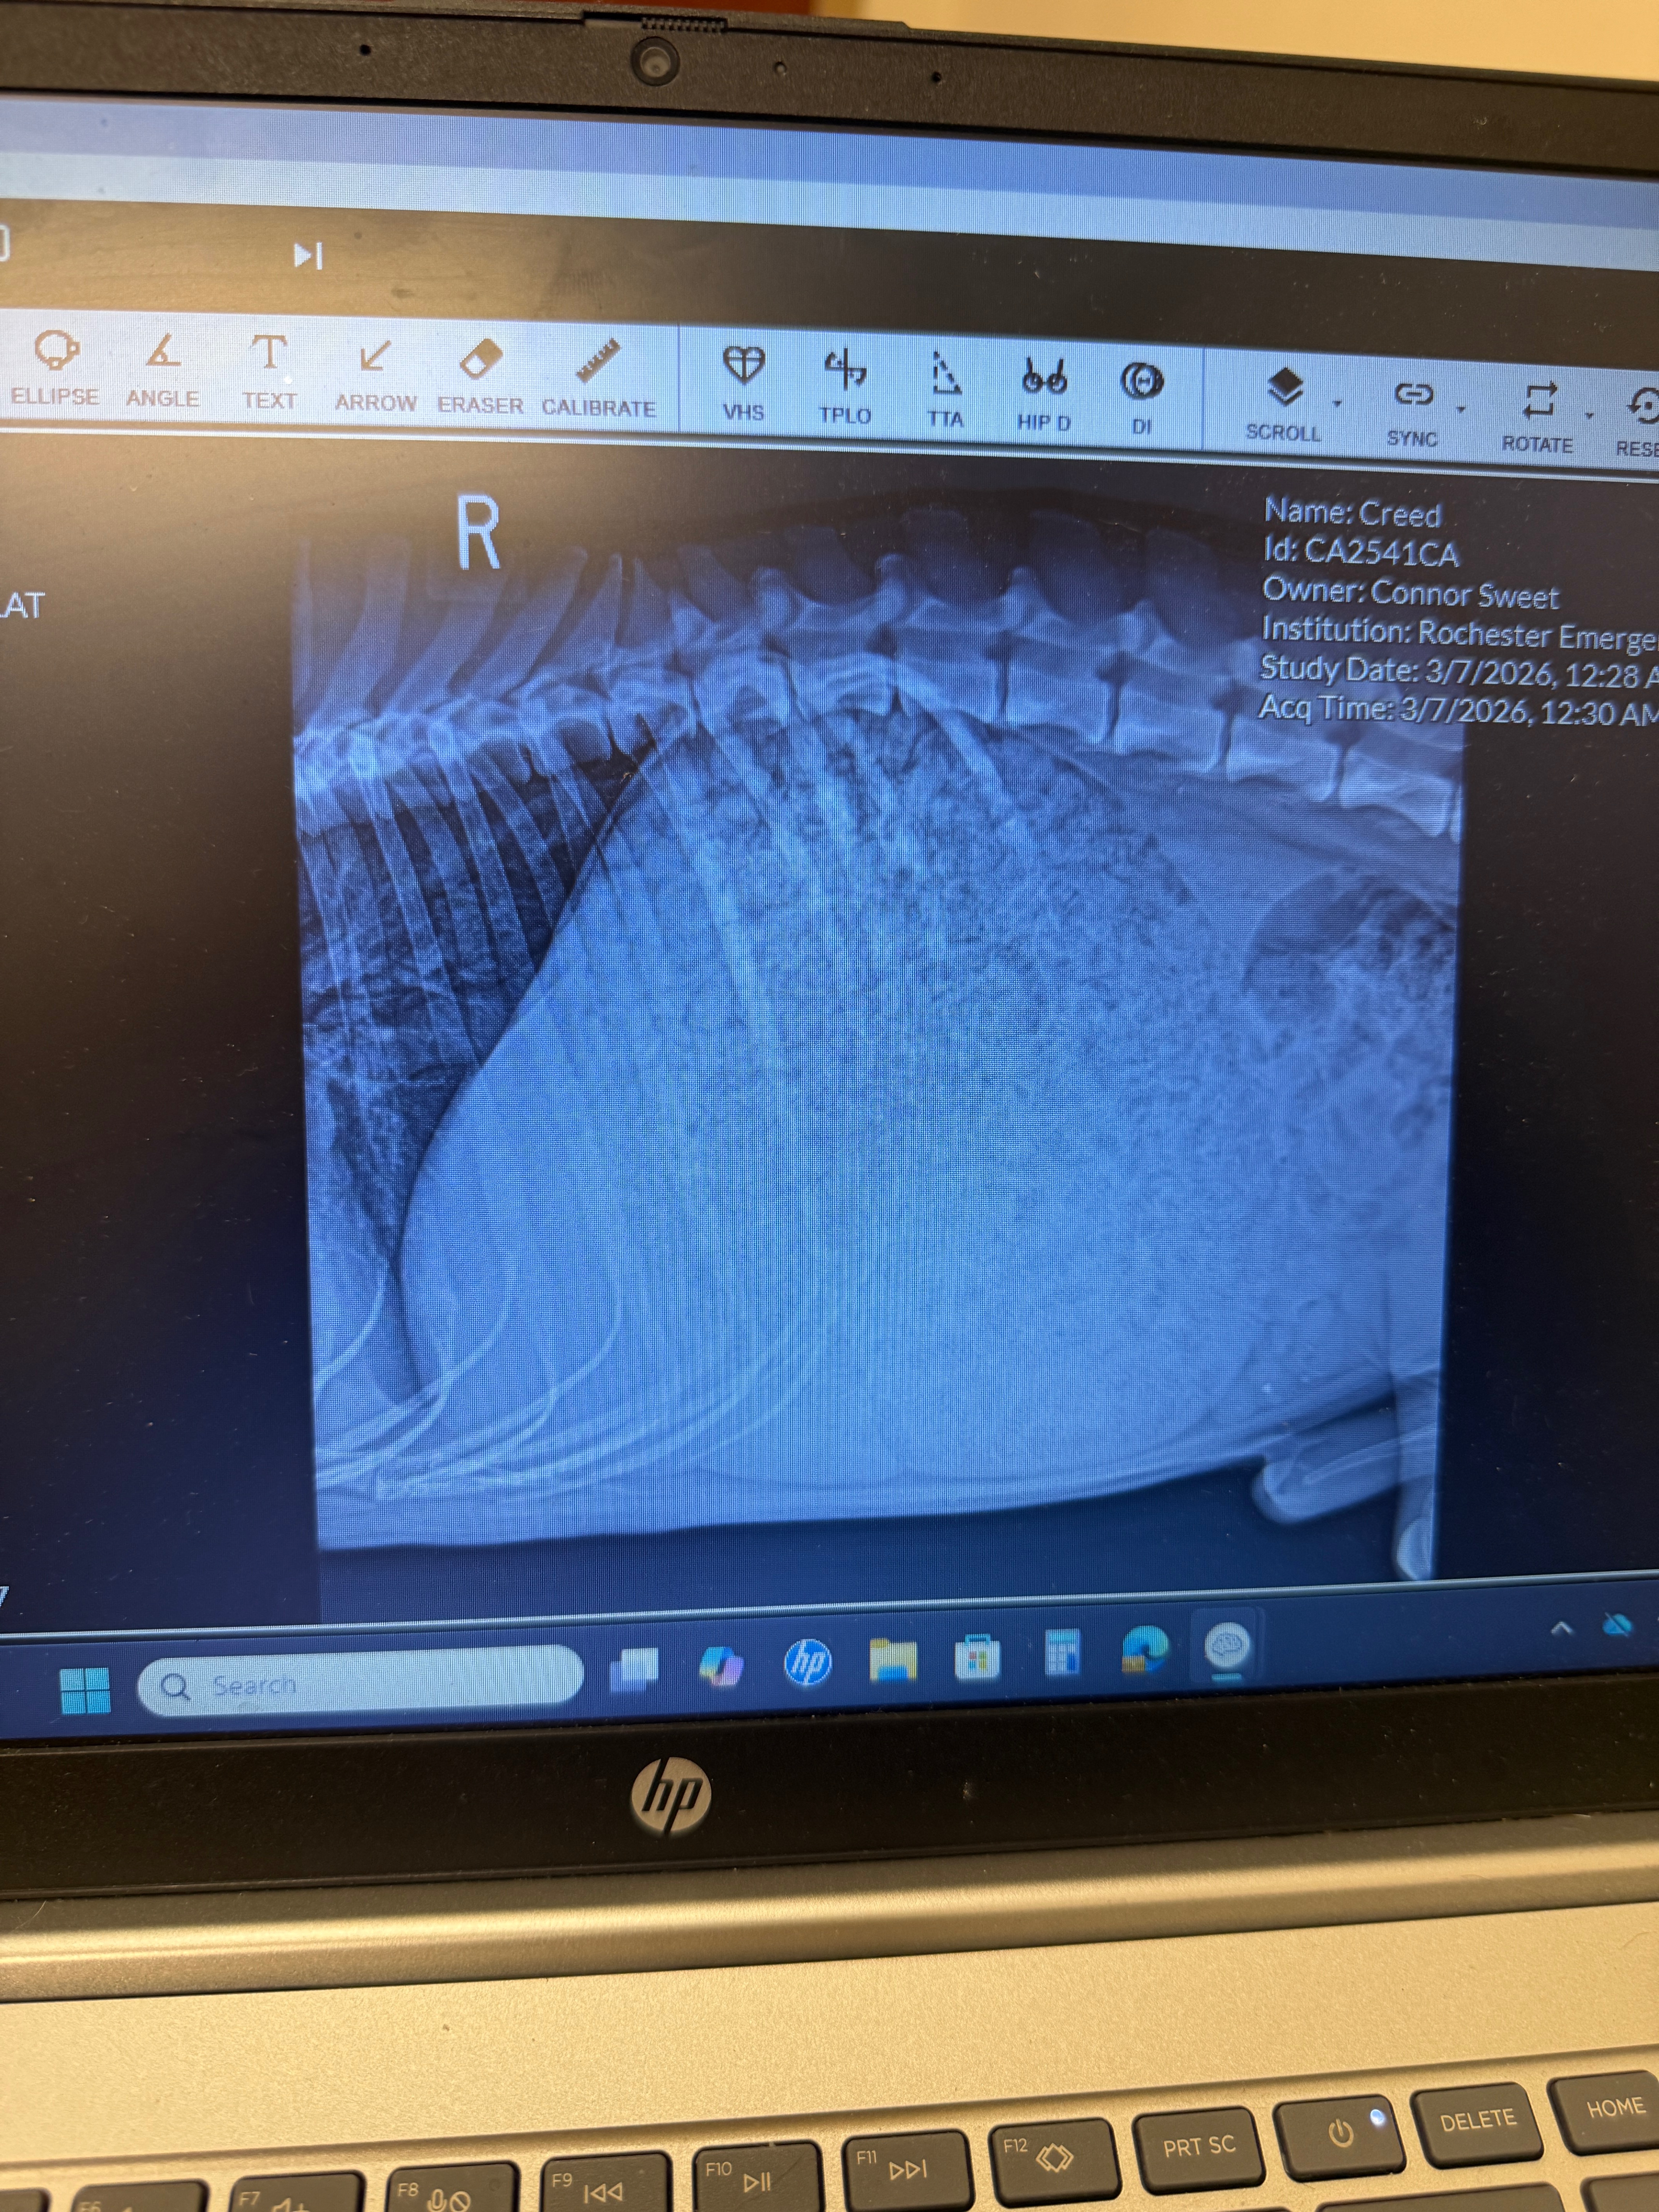

When we arrived around midnight, the emergency vet felt Creed’s lower stomach and immediately took him to the back room. He received a series of x-rays and an initial examination. To help him stay calm and comfortable, Creed had to be sedated and was given IV fluids. Creeds stomach was 3x the size of a normal stomach, for a deep chested GSD. His stomach was so large it was pushing his other organs together. He’s currently recovering overnight at the vet.